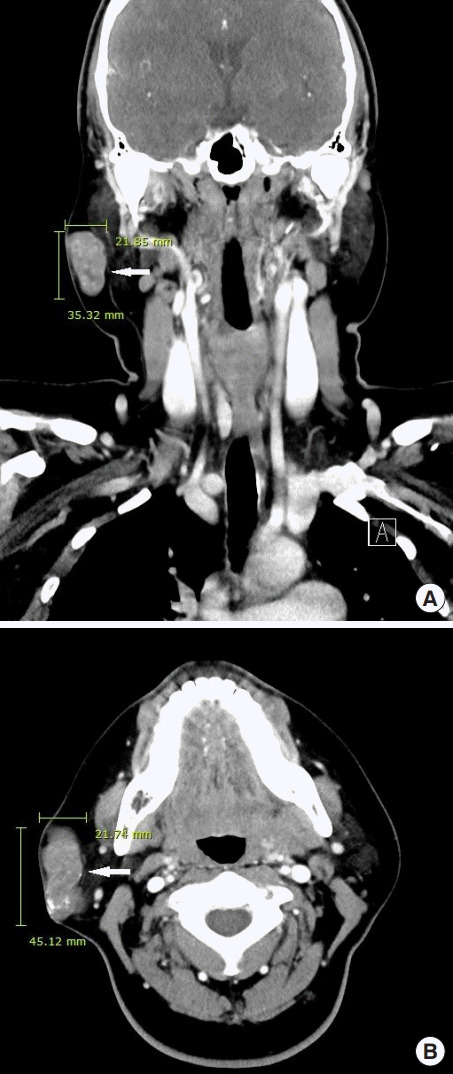

進行超聲檢查以確定腫塊是否為腮腺腫瘤,并顯示與腮腺分離的異質(zhì)腫塊(圖 2)。 進行了頸部對比增強計算機斷層掃描和超聲引導(dǎo)穿刺活檢。 在右下頜角,它表現(xiàn)為邊界清楚、分葉狀和不均勻強化的腫瘤,在皮下脂肪層和淺表肌肉腱膜系統(tǒng)中有鈣化部分(圖 3)。 穿孔活檢顯示與毛母質(zhì)瘤一致的特征,并且在超聲引導(dǎo)下對頸部淋巴結(jié)進行抽吸活檢時未發(fā)現(xiàn)腫瘤細(xì)胞。

An external file that holds a picture, illustration, etc.

Object name is acfs-2019-00710f2.jpg

圖 2:超聲檢查顯示與腮腺分離的異質(zhì)性病變

Object name is acfs-2019-00710f3.jpg

圖 3:頸部對比增強計算機斷層掃描的冠狀 (A) 和軸位 (B) 視圖顯示右腮腺區(qū)域(箭頭)中邊界清楚、分葉狀、不均勻的病變。